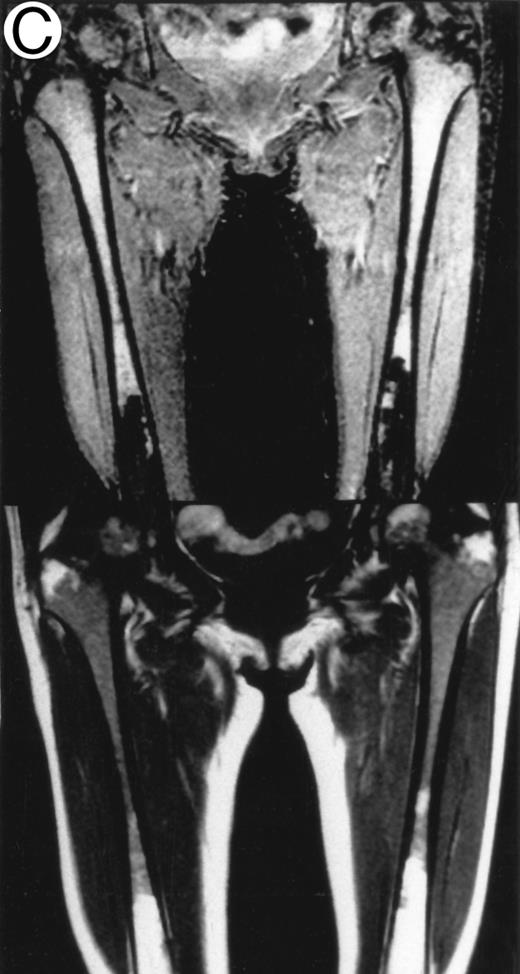

MRI.MRI was performed using SE sequences with the whole-body coil in a 1.5 tesla superconducting system (MRT 200FX/II; Toshiba, Tokyo, Japan). Coronal T1-weighted SE images of the femur were obtained in contiguous 10-mm slices in a 256 × 256 matrix with TR, 400 ms; TE, 20 ms; and number of signal acquisitions, 2. Tissues with short proton T1, such as fatty tissue, have a high signal intensity and appear bright on T1-weighted SE images, whereas those with a long T1, such as cellular marrow, have a low signal intensity and appear dark. STIR coronal images of the femur were obtained in 10-mm slices in a 256 × 256 matrix with TR, 1,500 ms; TE, 20 ms; and TI, 150 ms. On STIR images, the signal from fatty tissue is eliminated, whereas the signal from tissues with a longer T1 is progressively brighter. The MRI results were evaluated blindly by two independent observers who had no knowledge of the patients' marrow histology, tumor type, or stage. The MRI was classified as positive when both observers classified the T1-weighted SE images and STIR images as abnormal. The positive findings on femoral marrow MRI were categorized as follows: nodular pattern, characterized by nodular areas of fatty marrow replacement with a signal intensity that was lower on T1-weighted SE images (higher on STIR images) than that of muscles; scattered pattern, characterized by multiple scattered foci of marrow replacement on a background of uninvolved marrow; and uniform pattern, characterized by a uniform replacement of fatty marrow (Fig 1).

Patterns observed on femoral marrow MRI. (A) Nodular (arrow), (B) scattered, and (C) uniform. Top: STIR images and, bottom: T1-weighted SE images.

MRI patterns of femoral marrow.MRI findings of the femoral marrow were classified into three patterns as shown in Fig 1. Of 29 patients with a positive MRI, 21 (72%) exhibited a scattered pattern (Fig 1A), 6 patients (21%) demonstrated a uniform pattern (Fig 1B), and 2 patients (7%) exhibited a nodular pattern (Fig 1C). Of the 17 patients with positive results on BM biopsy, 11 demonstrated a scattered pattern on the MRI, and 6 patients showed a uniform pattern.